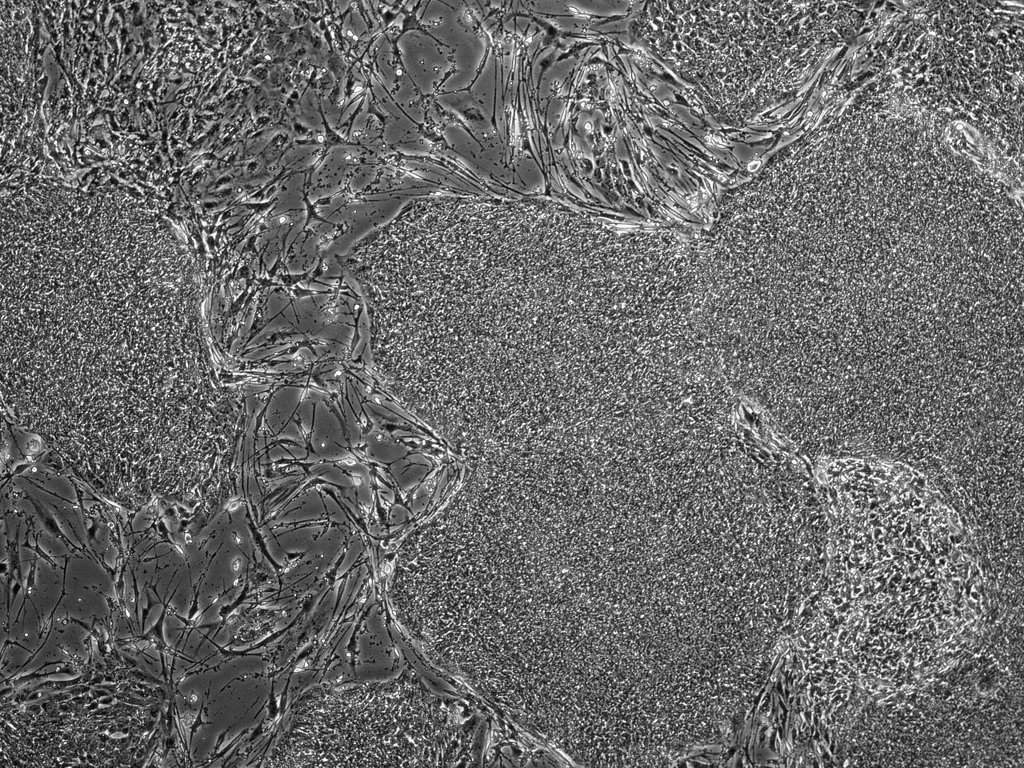

Các nhà nghiên cứu từ lâu đã có thể đưa tế bào người vào động vật, như kiểu họ đưa những mẩu nhỏ của các khối u ung thư vào cơ thể chuột để thử nghiệm các loại thuốc. Tuy nhiên, nghiên cứu tế bào gốc về cơ bản có sự khác biệt. Các tế bào gốc của người sẽ được đưa vào phôi thai đang phát triển, nơi chúng có thể trở thành bất kỳ tế bào nào, chẳng hạn như tế bào của các cơ quan, máu và xương.

Tuy nhiên, chi phí quá cao, đòi hỏi kỹ thuật quá phức tạp nhưng lợi ích mang lại chưa đủ để tạo ra những cơ quan có thể cấy ghép, khiến các nhà khoa học nghĩ đến một giải pháp táo bạo được cho là tối ưu hơn: nuôi nội tạng người trong cơ thể động vật. Ý tưởng là tạo ra một phôi lợn không có khả năng phát triển ở một cơ quan nào đó, chẳng hạn như tim. Tế bào gốc của con người sẽ được tiêm vào phôi thai này, sau đó phát triển thành một trái tim người bên trong cơ thể lợn.

Mặc dù đã hình thành trong nhiều thập kỷ qua, ý tưởng này gần đây mới trở nên phổ biến hơn, bắt nguồn từ loạt các thí nghiệm của Hiromitsu Nakauchi tại Đại học Tokyo (Nhật Bản). Nhóm của ông đã thành công trong việc phát triển tuyến tụy chuột bên trong một cá thể chuột khác loài. Thành công của Nakauchi khiến các nhà khoa học trong cùng lĩnh vực trở nên háo hức với với loại nghiên cứu này. Pablo Ross tại Đại học California, Davis (Mỹ) sau đó cũng đã tiến hành tiêm các tế bào gốc của người vào phôi lợn, duy trì cho nó tồn tại 28 ngày trước khi bắt đầu quá trình phân tích.